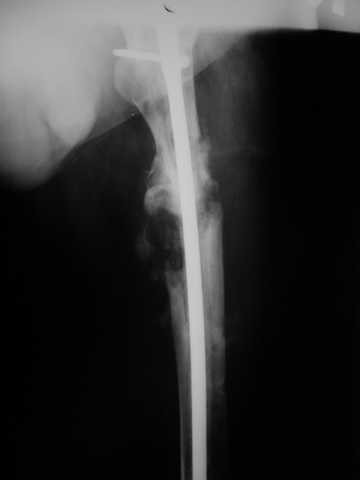

Мы демонтировали спице-стержневой аппарат, рассверлили костно-мозговой канал (до 14 мм), установили в канал спейсер с антибиотиком и произвели его блокирование четырьмя винтами ( рис. 1, 2, 3, 4).

В качестве армирующего элемента для спейсера мы использовали титановый неканюлированный штифт типа UFN (диаметр 9 мм, длина 400 мм). Проксимальную широкую часть штифта костным цементом не покрывали (рис. 5).

В остальном, операция прошла без технических трудностей. Александр Николаевич, спасибо за ваши прекрасные развертки. Так не хочется отдавать их Вам обратно! Завтра пациент выписывается. Температура тела и анализы у него нормальные. Бедро мягкое, отечность тканей значительно уменьшилась. Послеоперационные раны зажили первичным натяжением. Укорочение конечности составляет 1,5 см (по ощущениям больного, это оптимальная длина ноги для него, так как у него анкилоз коленного сустава и голеностопного сустава в положении подошвенного сгибания). Пациент ходит с дозированной нагрузкой на конечность (10% от веса тела). Свищ на передне-наружной поверхности средней трети бедра, который открылся за неделю до последней операции рядом со стержнем аппарата, закрылся 5 дней назад (рис. 6,7, 8).